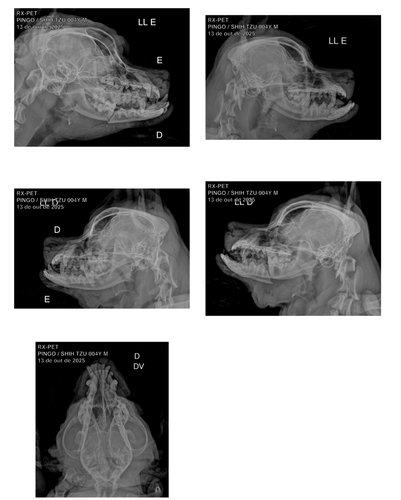

O Pingo está com a pata machucada e a boca ferida — um dos dentes inferiores acabou encravando na parte de cima, o que está impedindo ele de comer direito.

Levamos ele ao veterinário, e o Pingo precisará ficar internado para realizar uma cirurgia na boca (maxilar que foi quebrado) e receber medicação.